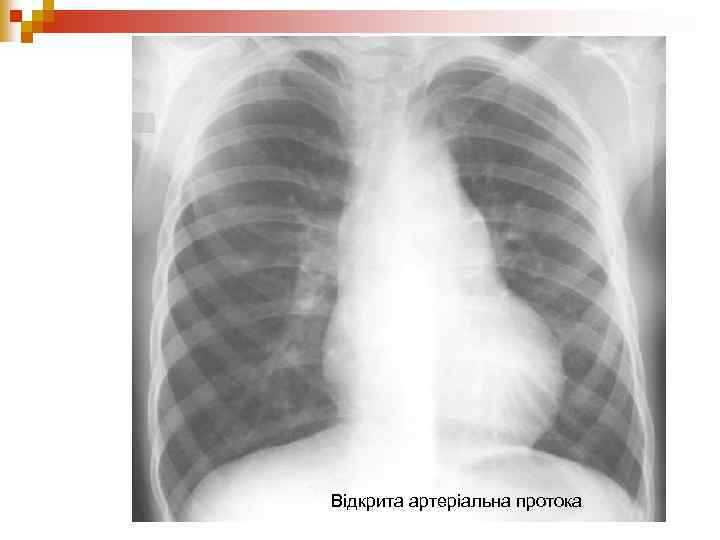

Відкрита артеріальна протока

n Серце злегка збільшене, основа легеневої артерії і дуги аорти випукла. Збагачення легеневого судинного малюнку